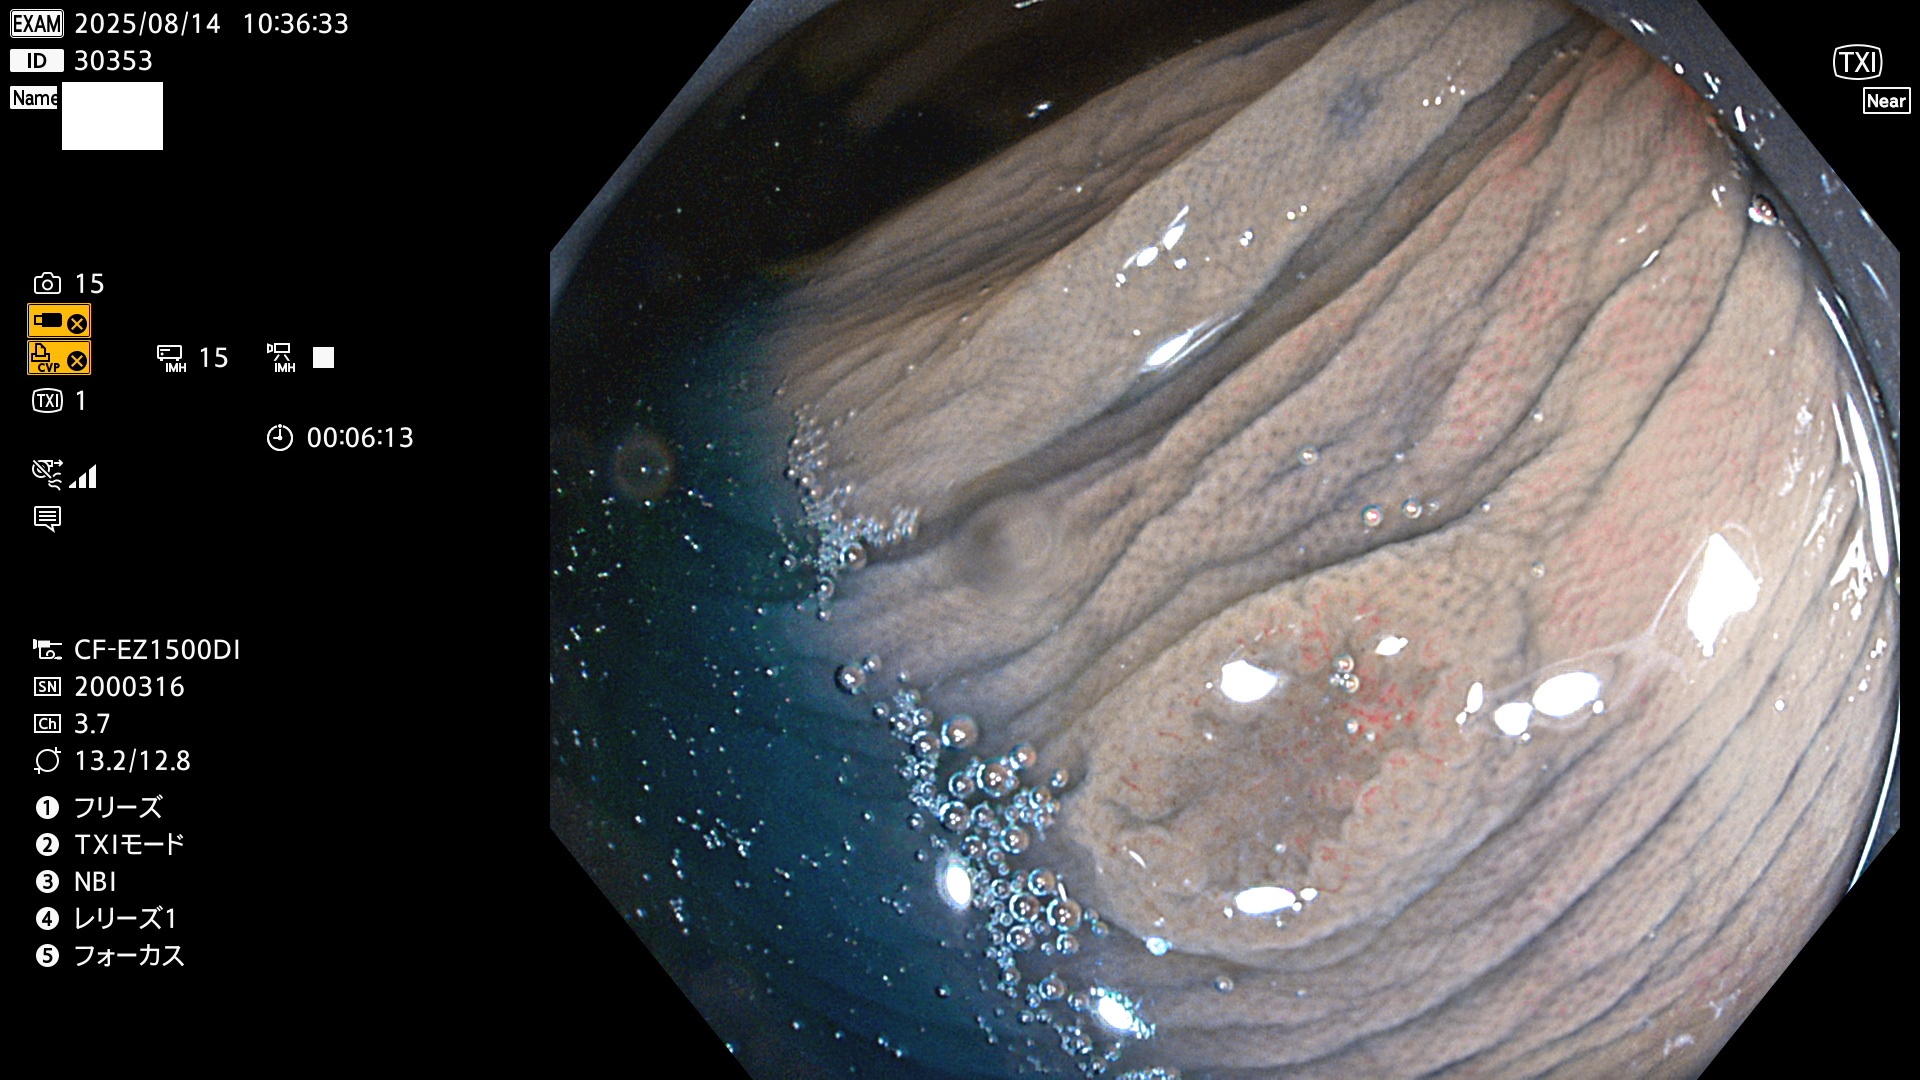

完全に平坦な物をUb、陥凹している物をUcと呼びます。Ubは認識が困難で、Ucはびらん(炎症)と紛らわしいために見落とされやすく、「内視鏡後・大腸癌」の原因になります。

専門的)Uc=De Novo癌? 内視鏡の解像度が低かった時代、このような説もありました。しかし今日の高精度内視鏡では良性の微小なUc型腺腫(APC遺伝子異常の腺腫)が日常的に見つかります。Ucこそが多段階発癌(Adenoma-Carcinoma Sequence)のMain Routeです。

2025年8月14日〜8月17日の4日間(30件)3個 (Uc_ADR=3個/30人=10%)